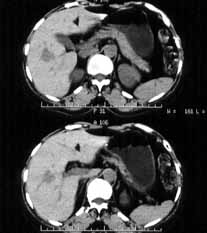

肝血管瘤06

女性,55岁,右上腹间有隐痛不适半年余。

ct诊断:肝右前叶下段血管瘤。